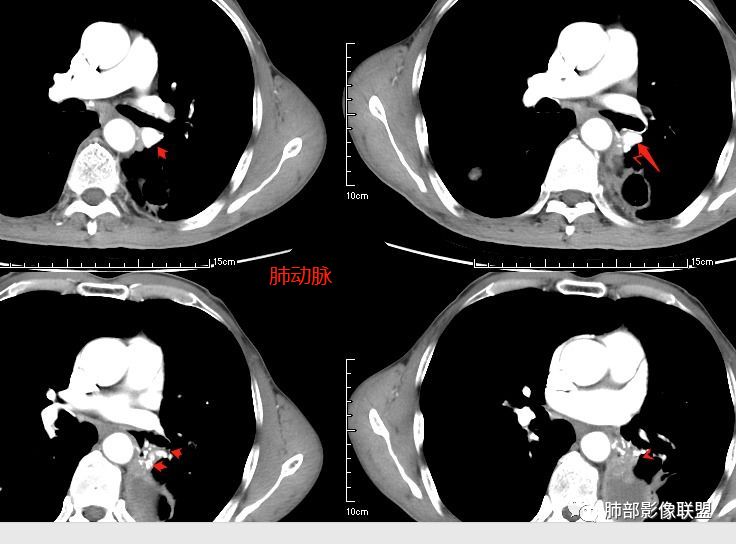

患者老年男性,咳嗽、咳痰、痰中带血伴胸闷2月余。长期大量吸烟史。查肝肾功能、血糖、血脂、心肌酶、电解质、血沉、C反应蛋白、抗“O”、类风湿因子、抗核抗体谱无明显异常。肿瘤标志物提示NSE、CYFRA21-1稍升高。胸部CT:肺气肿背景,左肺下叶后基底段不规则肿块影,见支气管截断,内见大片状低密度区及部分血管影,增强轻度强化,远端空洞形成。双肺多发不规则实性结节影、见毛刺、胸膜牵拉及血管集束,结节内见空洞形成,部分可见血管影,多位于胸膜下。双肺见多发肺大泡。综合考虑左下肺恶性病变并双肺转移。鳞癌或淋巴瘤可能。鉴别血管炎性病变及真菌感染。

张延军:双肺多发结节,空洞影,后者洞壁厚薄不均匀,部分腔内丝丝落落,呈分叶征,边缘见毛刺影,病灶大部分位于胸膜下,与血管相连,右肺下叶前基底段结节近段支气管截断,远端见空腔。左肺下叶病灶密度不均,背段支气管壁增厚,管腔狭窄。考虑1.双肺下叶占位性病变伴肺内空洞性转移 2.多原发的占位 3.肉芽肿性血管炎代排。

这个病灶如何分析?

三个石头:都有血管从凹陷处进入

张玉:收缩,牵拉,血管增粗,与血管相连

南边:我们再看看左下叶背段的病灶

南边:

大家按我提的单个病灶分析,很多提出来都是典型的腺癌

脐凹征、粗短毛刺、深分叶、中央结构杂乱

本病例左肺下叶肿块,有深分叶、毛刺、胸膜牵拉凹陷、支气管截断及纵隔内淋巴结肿大等征象,都均支持病灶为恶性,如腺癌,而且叶间裂的多发结节也提示是腺癌来源可能大;双肺多发结节、肿块,大部分病灶有分叶、毛刺及胸膜凹陷的恶性征象,与原发肿瘤本身的性质有关,所以应该与左肺下叶肿块同源,而且双肺多发病灶内空洞也具有多样性;